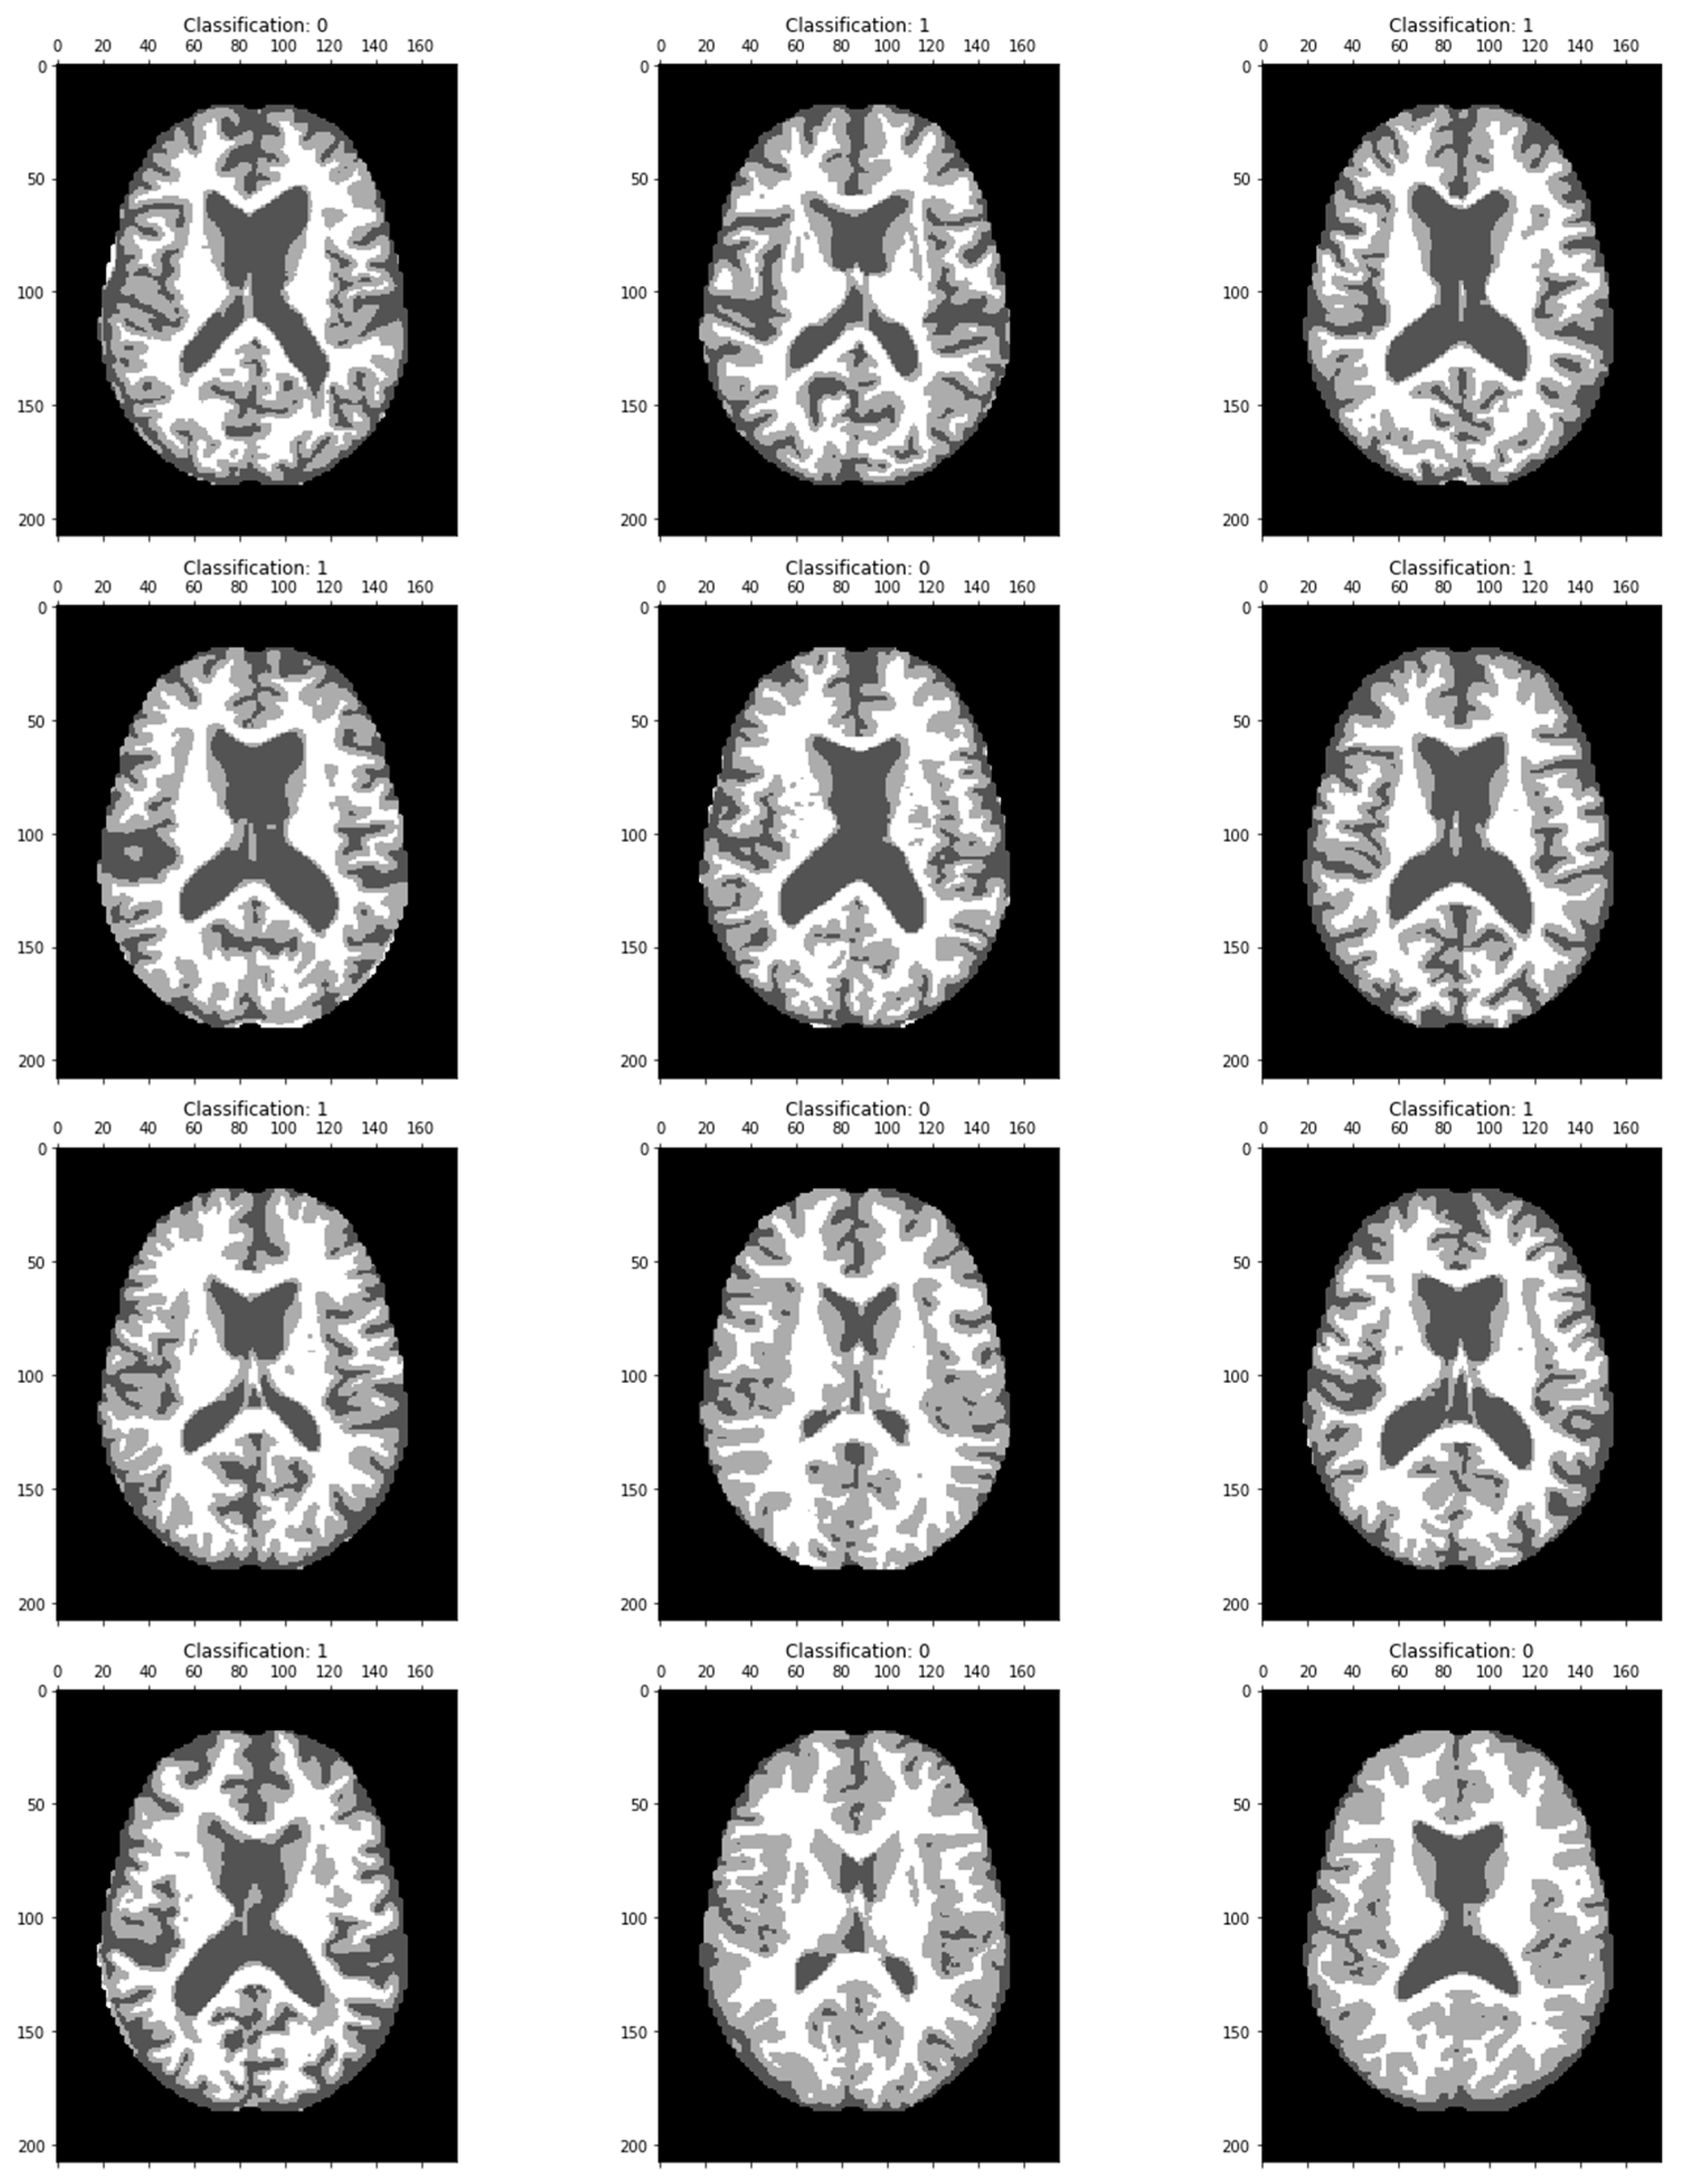

The MRI image classified results are displayed in Figure 7. Dementia has been classified in each image as a particular region.

Figure 7.

MRI image classification results showing the classification value as 0, confirming the absence of Alzheimer’s disease, and Classification 1 shows the brain image of an Alzheimer-affected person.